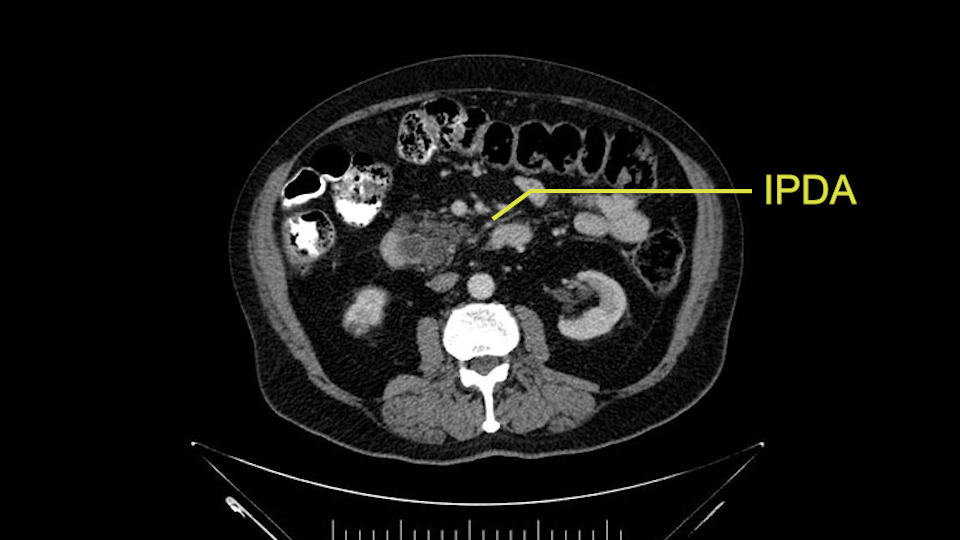

Other important points are: the dissection of the uncinate process which must be done very carefully, the ligation of the venous branches there, and looking for the inferior pancreaticoduodenal arteries coming from the superior mesenteric artery during the dissection of the uncinate process.

Uncinate margin, IPDA

Once the pancreatic neck is divided, you sort of roll or flip the neck of the gland over, exposing the anterior surface and the right lateral surface of the portal vein-SMV complex. Continue that dissection down. Oftentimes you can really continue your dissection right along the uncinate on the SMA. Again a little advantage of this patient having an ampullary lesion, there's likely to be no evidence of extension into the uncinate so you don't have to worry quite as much about the margin at the uncinate as you would with a pancreatic head cancer. Keeping in mind that you will have an inferior pancreatic duodenal artery in there that you want to try to identify and ligate individually. At some point along that time I go to the ligament of Treitz. Clean an area of the ligament of Treitz of its mesentery, divide it there with a linear stapler. I use the Harmonic scalpel to mobilize the proximal 10-inches or so of small intestine down to the ligament of Treitz completely mobilize the ligament of Treitz past the jejunal limb underneath the root of the mesentery and then carefully dissect the third and fourth portion of the duodenum’s mesentery as well as the remaining uncinate to complete my resection. I will have marked and sent frozen section from the pancreatic neck at the time that I do the resection of that part of the gland so that I have that information back by now. I would also probably get a margin on the uncinate and a margin on the bile duct just for completeness, although for an ampullary carcinoma that would be unlikely to have a positive extension.